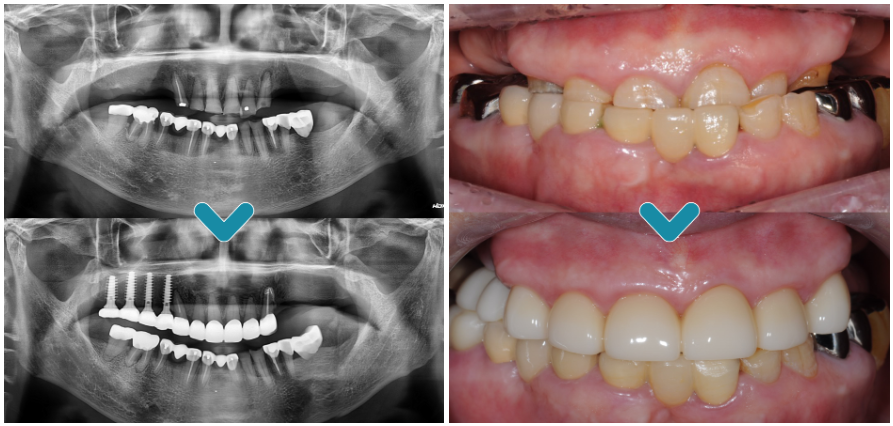

임플란트를 식립 할 때 위아래의

교합을 정교하게 맞추기 위해 아래쪽

보철물을 새로 제작하였으며,

.

닳아있던 앞니 보철치료까지 완료하여

2년 후 정기 검진을 오셨을 때

촬영한 파노라마 사진입니다.

매직 코어 임플란트의 식립을

통해 빠른 회복과 더불어 환자분의

꾸준한 관리로 건강하게 유지가

잘 되고 있음을 알 수 있었습니다.

어금니의 임플란트와

앞니 보철치료까지

완료되고 난 후에는 기존 거꾸로

물리고 있었던 교합까지

회복할 수 있었습니다.